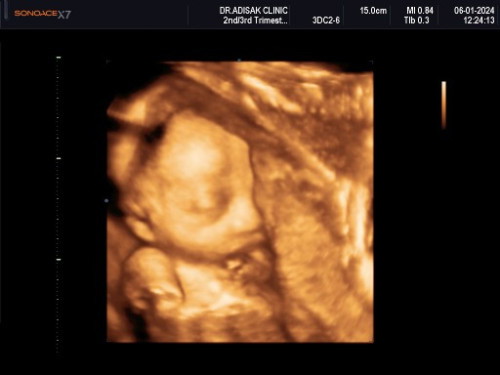

กำหนดคลอด9มีนาจ้า บ้านนี้ได้ลูกสาวแม่ๆทีมมีนาแต่ละบ้านได้ลูกชายหรือลูกสาวกันค่ะ